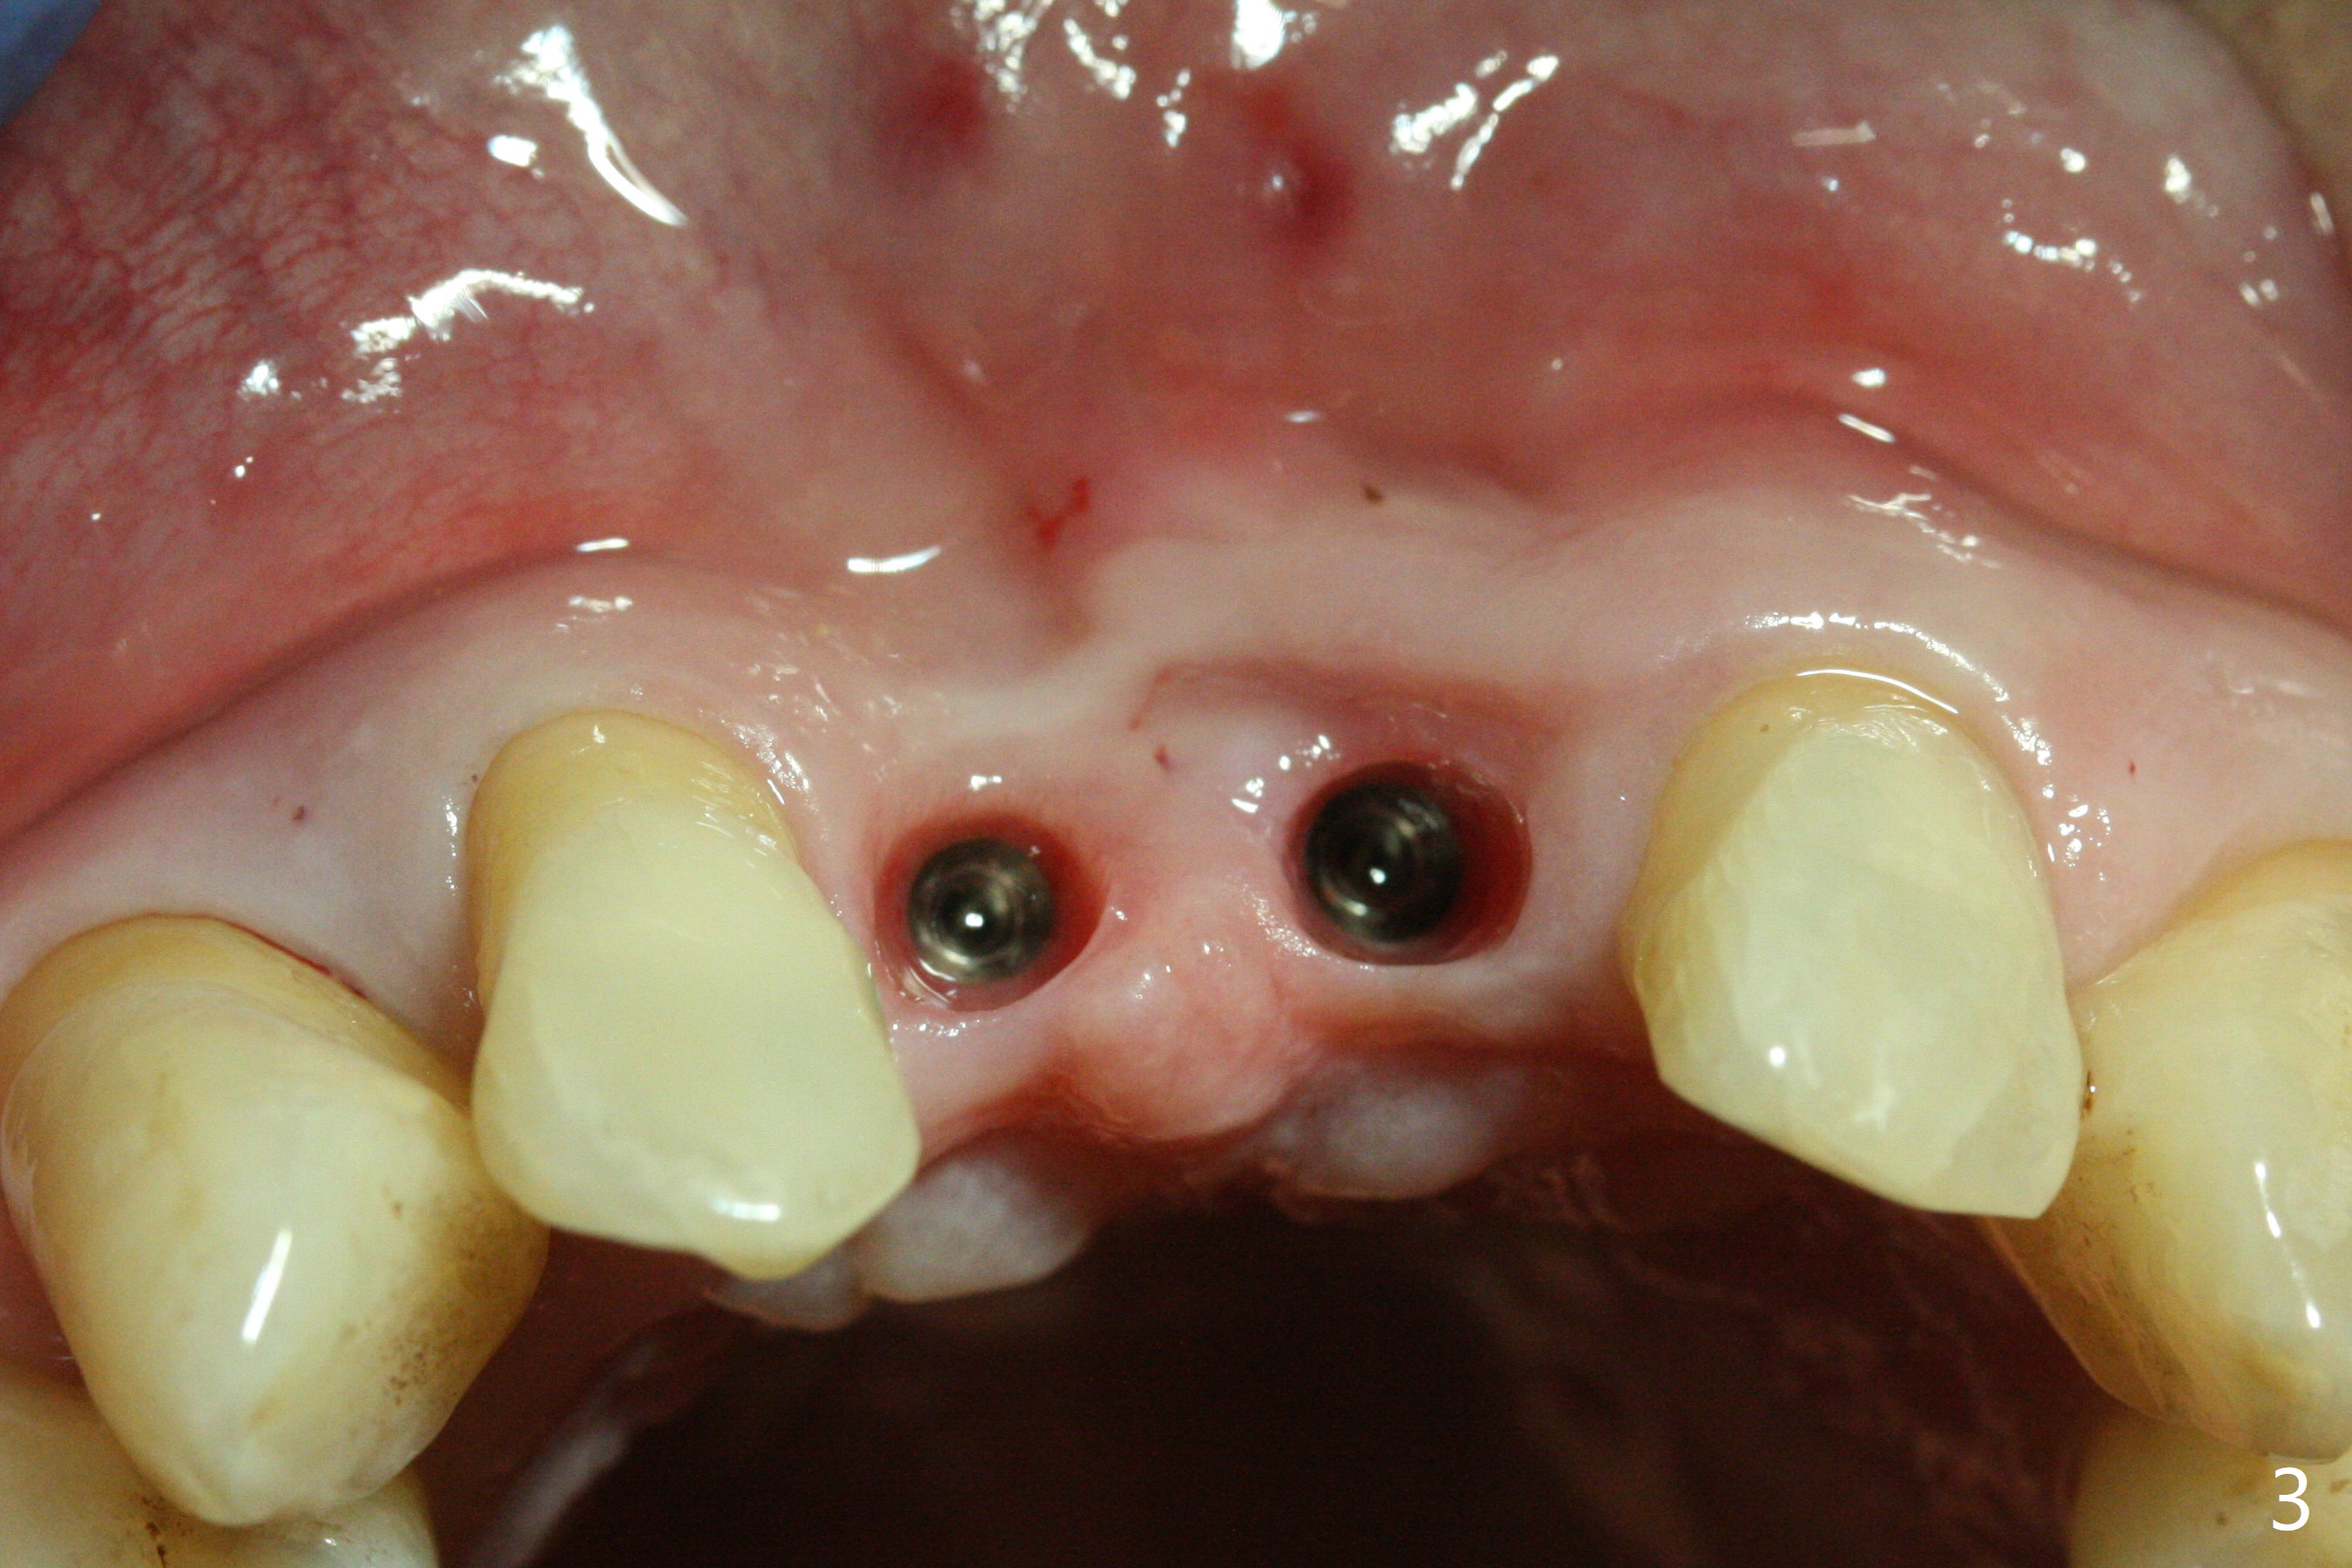

The gingiva remains recessive at #8 and 9 six months post immediate implant placement with bone graft (Fig.1). The buccal plate at #8 is particularly concave before (Fig.2 *) and after (Fig.3) abutment removal. The bony defect repair is assisted by placing a 4 mm tenting screw between the 2 implants (Fig.4) and placing allograft mixed with PRF (as putty) around the screw (Fig.5 (after replacement of the abutments)). The buccal contour improves because of the tenting screw and the bone graft placement (Fig.6 (as well as PRF and 6-month membranes)). The wound dehisces 12 days postop and immediately before leaving country for months (Fig.7). The sutures are removed, Osteogen plug is inserted (Fig.8) and periodontal dressing is applied (Fig.9). PA is taken to show the tenting screw (Fig.10 T). The latter is exposed 3 months postop (Fig.11,12). It appears that gingival graft is a must (Fig.13). Make a palatal stent, remove the temp with abutments and create a bleeding surface before harvesting a large piece of tissue. Connective tissue graft is done 5 months post bone graft (Fig.14). In fact there is no implant thread exposure. In fact the connective tissue graft does not survive. The abutments are re-prepared for pink porcelain (Fig.15). The bone loss is stable 1 year post cementation in spite of incomplete abutment seating (Fig.16). The soft tissue is nearly normal (Fig.17).